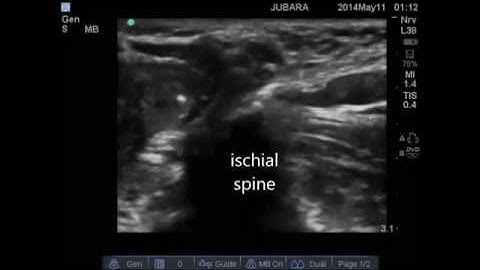

(Freemedbooks.com) Ultrasound Guided Pudendal Nerve Block for Children in the Lithotomy Position